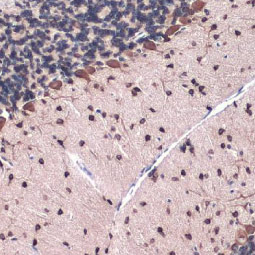

SOX2 antibody [GT1876] (GTX627404)

SOX2 antibody [GT1876]

(GTX627404)